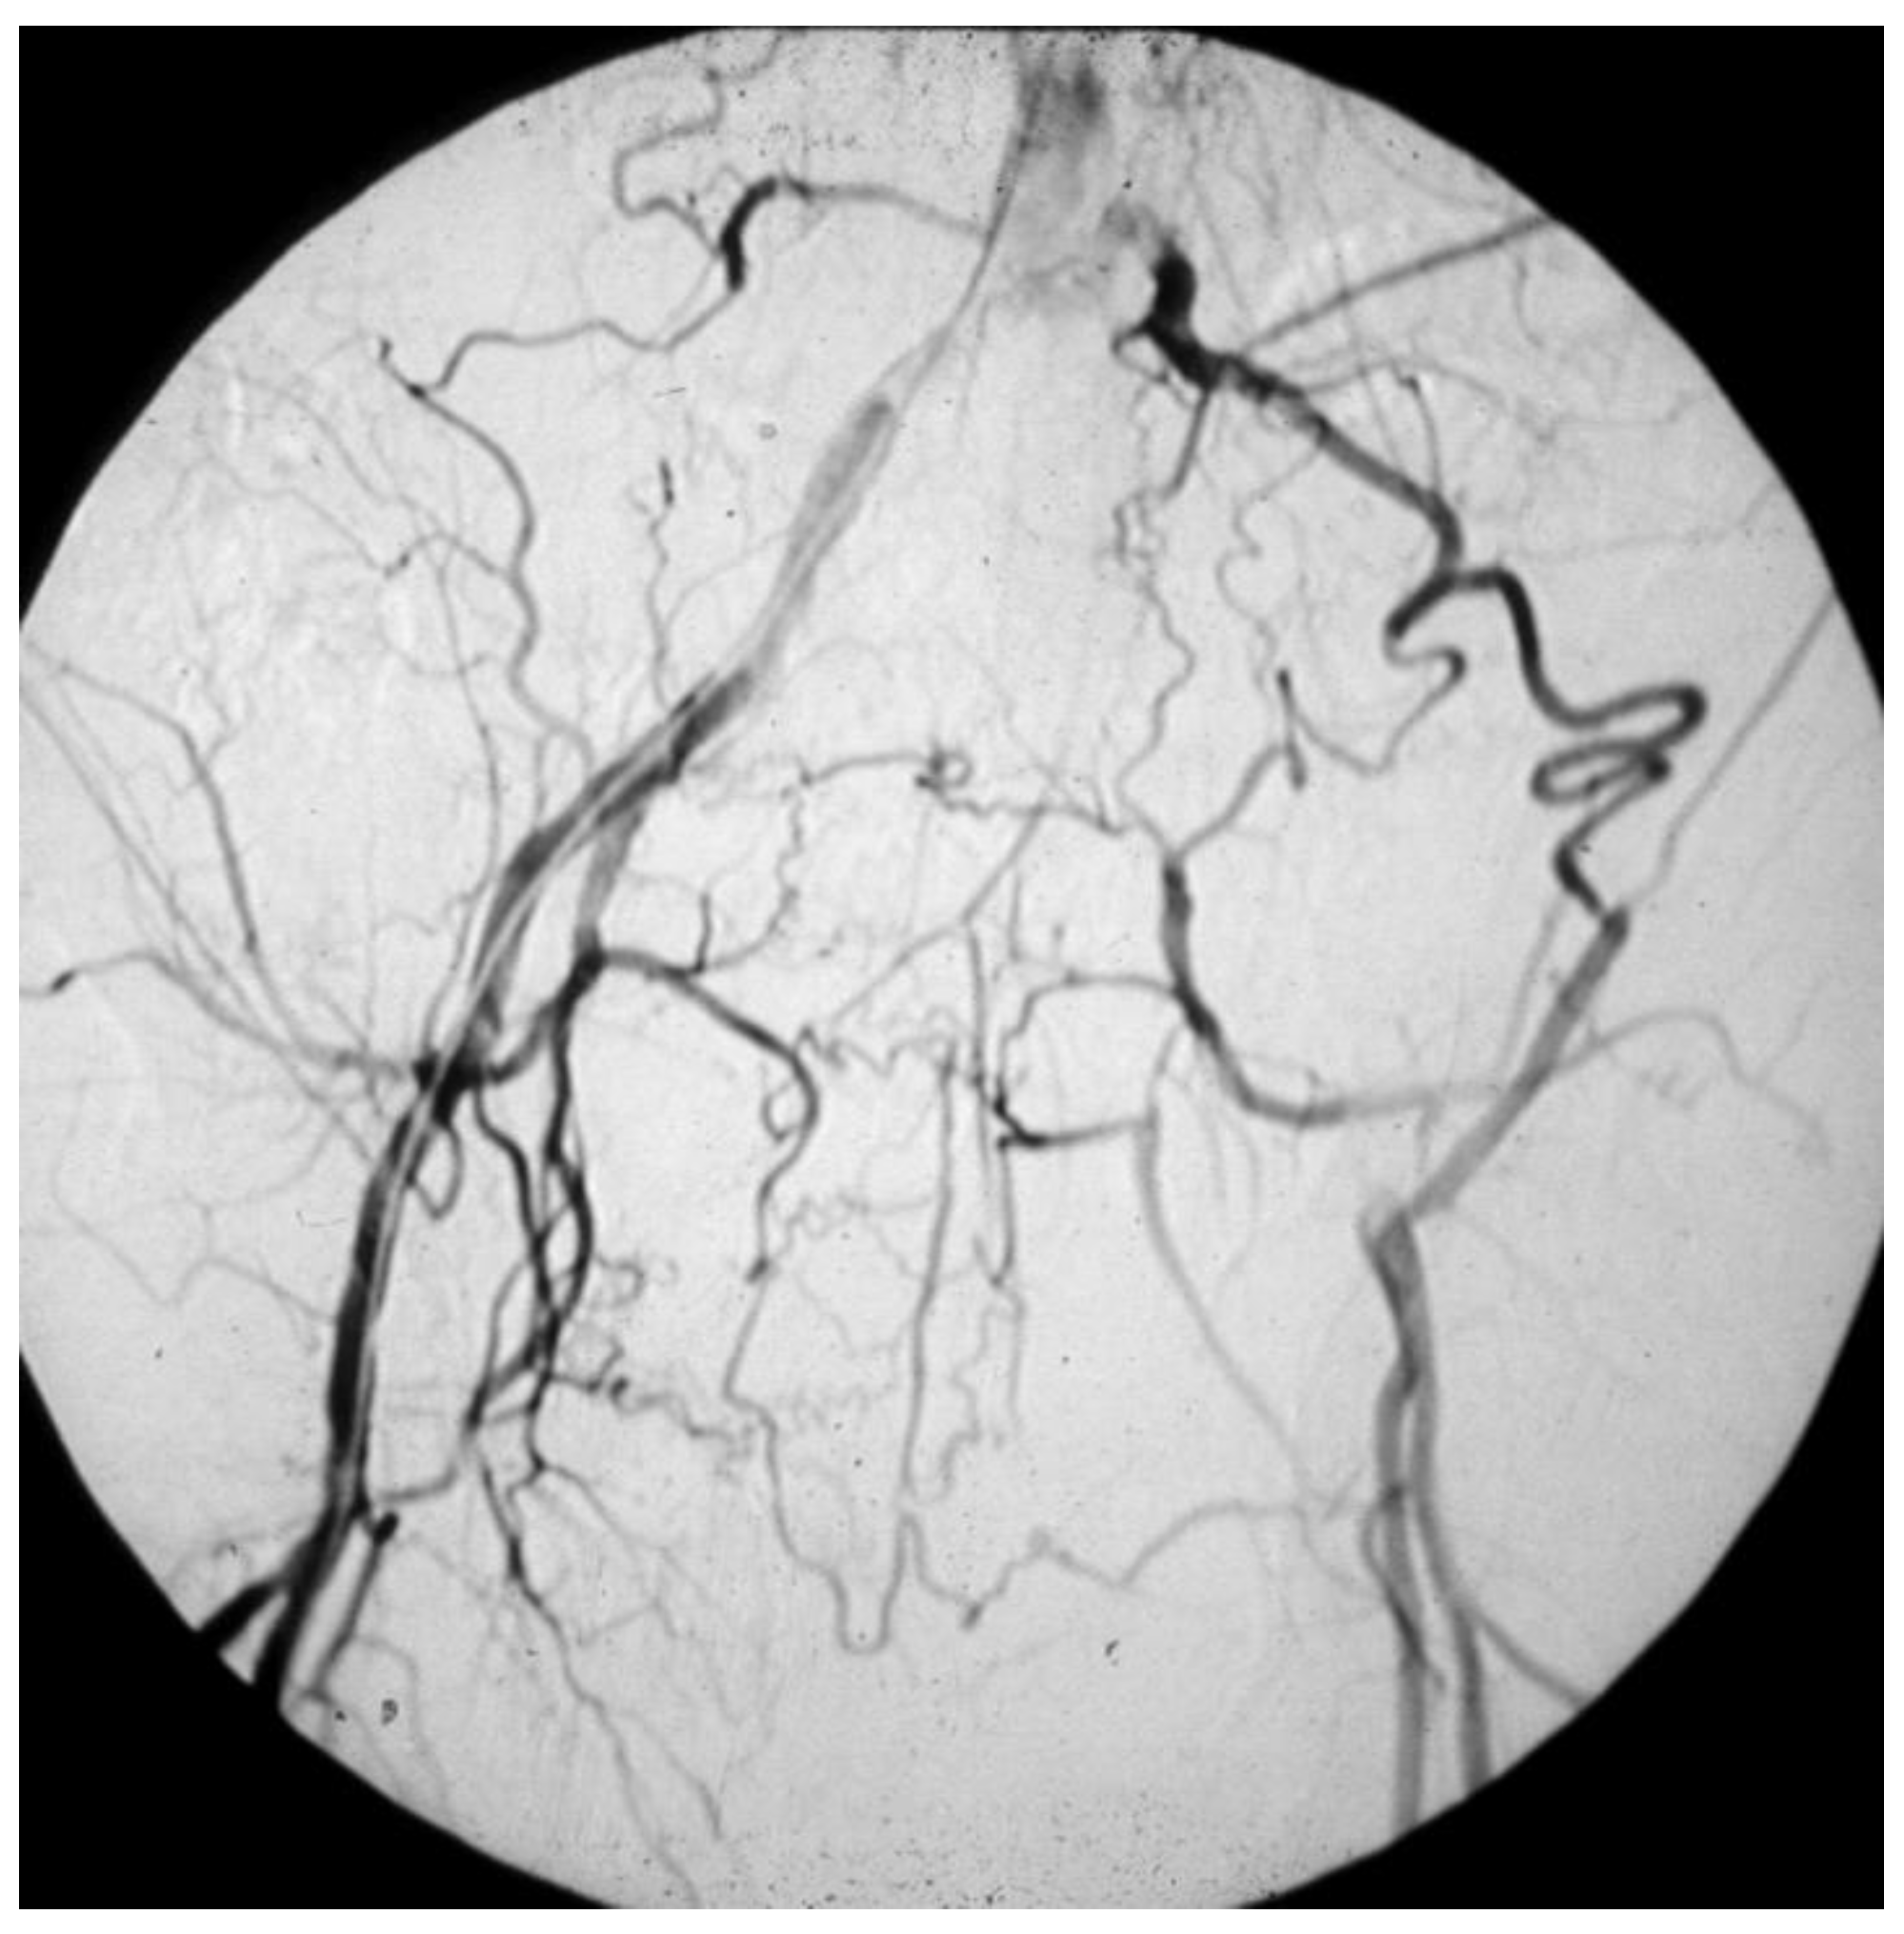

- Those who have a masked LEAD, since they do not present IC: reasons range from the development of efficient arterial collateral circulation (Figure 8) to limited mobility, up to being bedridden [51];

Figure 8. Arteriography showing obstruction of the left iliac axis, with an efficient collateral pathway revascularizing the common femoral artery. Depending on his/her age and lifestyle, this patient can eventually be asymptomatic or paucisymptomatic for intermittent claudication. An accurate physical examination (detecting the absence of the left femoral pulse), and the subsequent left ankle-brachial index (founded to be reduced) can easily allow for this patient to be classified as vasculopathic. - -